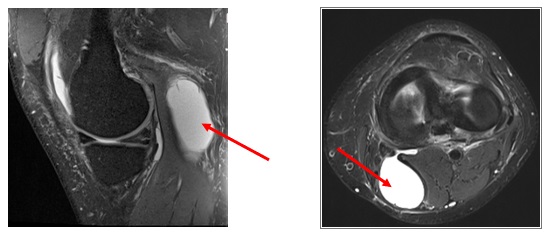

O Quisto de Baker, ou quisto poplíteo, consiste num quisto com líquido sinovial, de localização posterior no joelho.

O seu Ortopedista e Médico de Medicina Geral e Familiar poderão realizar o diagnóstico com o exame objetivo, mas habitualmente são pedidos exames complementares de diagnóstico como a Ecografia e a Ressonância Magnética.